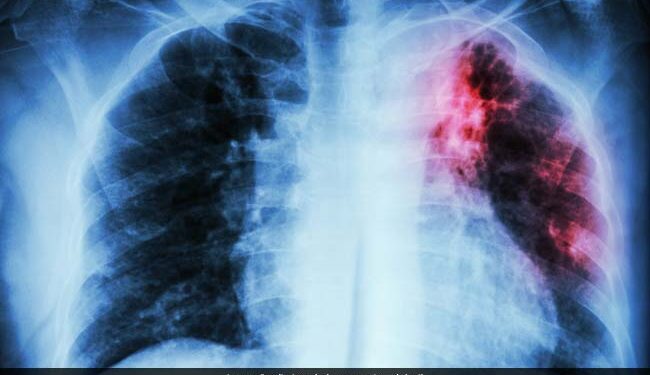

Chandigarh/New Delhi: The rate of tuberculosis (TB) incidence decline in India has doubled since 2015, surpassing the global average, Union Health Minister JP Nadda announced on Saturday. Speaking at the launch of a nationwide 100-day TB elimination campaign in Panchkula, Haryana, he emphasized the government’s commitment to combating the disease.

“India has made significant strides in TB elimination. Since 2015, the incidence decline has doubled from 8.3% to 17.7%, far exceeding the global average. Additionally, TB-related deaths have reduced by 21.4% over the last decade,” he added.